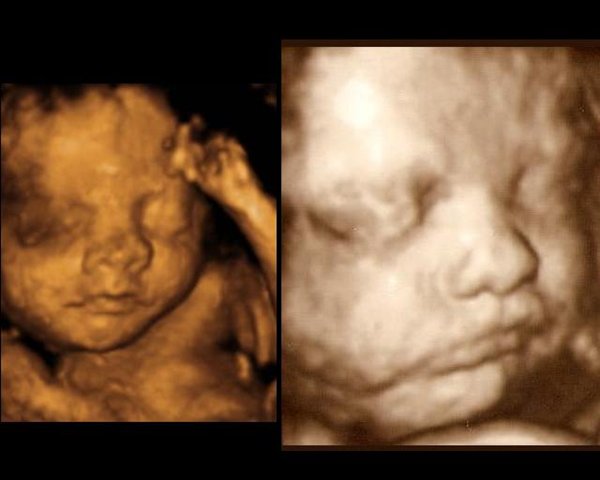

Til venstre ses lillesøster (Celina) i uge 27+3

Til højre på billederne er det storesøster (Bianca) i uge 29+3